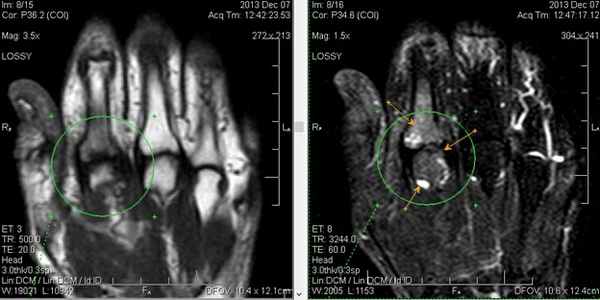

Результат МРТ правого лучезапястного сустава (рис. 2), подтвердил клиническое предположение о повреждении ладьевидно-полулунной связки, который заключался в нарушении целостности структуры связки. Также были выявлены признаки асептического некроза ладьевидной кости в стадии отека костной ткани.

Рис. 2. МРТ-исследование правого лучезапястного сустава. Получены протон взвешенные изображения с подавлением сигнала от жировой ткани (PD FAT SAT) в аксиальной, сагиттальной и фронтальной плоскостях, Т1 взвешенные изображения во фронтальной плоскости. На полученных сканах определяется: 1 – увеличение ладьевидно-полулунного сустава вдвое по сравнению с соседними; 2 – вдоль оси ладьевидной кости отмечается скопление жидкости, что можно расценить, как продольный перелом ладьевидной кости, либо отек костной ткани

Учитывая данные клинического осмотра и лучевых методов исследования, пациентке было рекомендовано оперативное лечение: реинсерция поврежденной ладьевидно-полулунной связки и фиксация ладьевидно-полулунного сустава при помощи биодеградируемого пина 1,5. Для фиксации связки был выбран биодеградируемый якорный фиксатор.

После операции лучезапястный сустав фиксировался иммобилизационной повязкой сроком на 4 недели. По окончанию срока иммобилизации пациентке была рекомендована постепенная разработка лучезапястного сустава, исключающая осевые нагрузки. Через 6 недель с момента операции пациентке было выполнено МРТ исследование для осуществления контроля положения восстановленной связки (рис. 5).

Рис. 5. МРТ исследование правого лучезапястного сустава. На МРТ сканах во фронтальной плоскости: 1) отмечается восстановление пространства между ладьевидной и полулунной костями, отчетливо видна связка; верифицируется биодеградируемый пин и якорный фиксатор в ладьевидной кости; 2) отмечается синовит лучезапястного сустава и отсутствие отека костной ткани ладьевидной кости